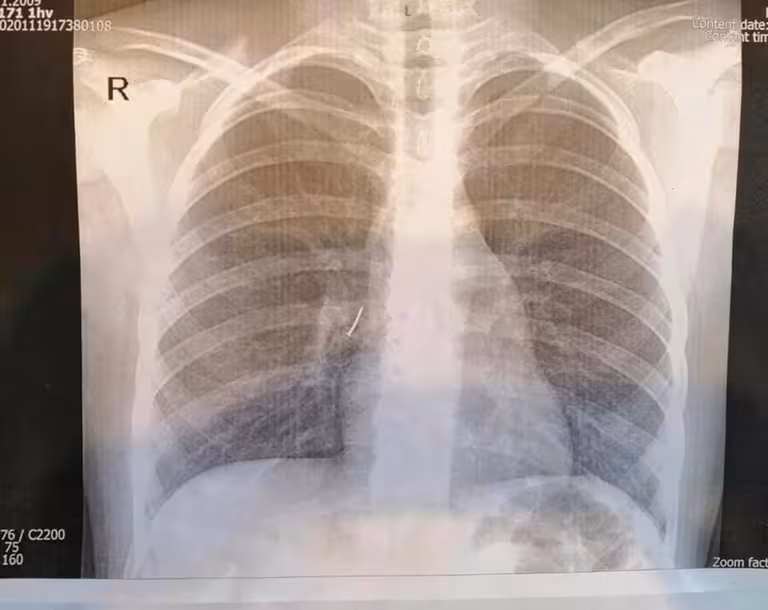

Пацієнтка з канцелярським цвяхом потрапила в ОХМАТДИТ, вночі дівчинку привезла швидка з Ходорівської міської лікарні. Дитині зробили рентген-знімок, інформація про стороннє тіло у бронху підтвердилися.

"Ми виконали ригідну трахеобронхоскопію під наркозом. Спеціальними ендоскопічними інструментами — щипцями під оптичним контролем — з правого проміжного бронха дитини ми дістали канцелярський цвях з пластмасовою частиною і гострим вістрям. То було непросто, адже пластмасова частина цвяха повністю перекрила бронх так, що нижня доля правої легені майже не функціонувала", — розповів Олександр Колодій, який займався порятунком дитини.